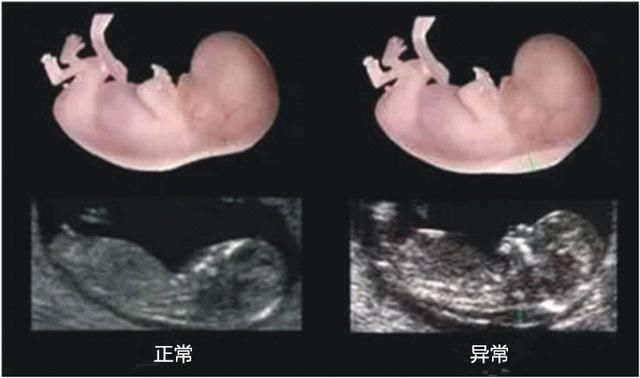

是指胎儿颈部一个透明的液体,可以用于早期唐氏综合征的风险评估。 患唐氏症的胎儿会有皮下积水的情况出现,因此颈部后面的皮肤会比较厚。如果NT检测出胎儿颈部皮肤厚

孕期NT检查,其实就是孕早期针对胎儿"颈项透明层"的检查方式,是评估宝宝是否可能有唐氏综合症的重要方法。这个检查跟孕期B超检查不一样,虽然都是超声扫描来做,但重点是为了在妊娠较早阶段诊断染色体疾病和发现多种原因造成的胎儿异常问题,对于预防胎儿先天性畸形很有帮助。 在深圳为数不多的几位专家获得了该技术的国际认证。在医学超声检查界这是唯一一项需要通过国际考试才可以检查病人的检测,而深圳恒生医院是深圳拥有NT检查资质医院的其中之一。深圳恒生医院产科是医院独具品质服务特色的精品学科,科室在为每一位孕妈妈提供医疗安全保障的同时,为孕妈妈提供温馨的人性化服务,让她们充分体验到即将做母亲和初为人母的喜悦心情。 温馨提示:NT检查的最佳时间为怀孕11-14周,错过了这个孕期则筛查达不到最好的效果,提前预约NT检查,可免排队挂号的困扰。一般来医院检查的孕妇大多数都是在周末,只有周末家人才有时间陪伴。提前预约挂号,可以节约时间。

病情分析: NT是指胎儿颈项后透明带宽度,是用B超筛查唐氏综合症的,结合血清学检出率达85%-90%,唐氏儿俗称傻瓜。因查NT是用B超所以费用也只是彩超的价格。 意见建议:建议早期的筛查不要遗漏,如果胎儿有畸形,出生后给家庭和社会带来得影响是很大的。定期产检,祝你宝宝健康。